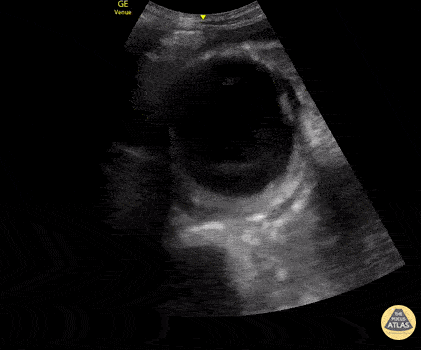

70s-year-old male brought in for altered mental status and hypotension. As part of the initial exam, POCUS was performed. This clip, obtained using the curvilinear probe in transverse orientation over the mid-epigastric region, revealed a AAA measuring 8 cm in AP diameter at the largest point with heterogeneous echogenic material consistent with thrombus. CT abdomen/pelvis with IV contrast confirmed ruptured AAA with thrombosis and only minor extravasation. In this case, POCUS played a critical role in the rapid diagnosis of a patient with undifferentiated shock, particularly in a patient who was unable to provide any history. Katherine Spencer, MD Guy Youngblood, MD, FACEP, FAAEM